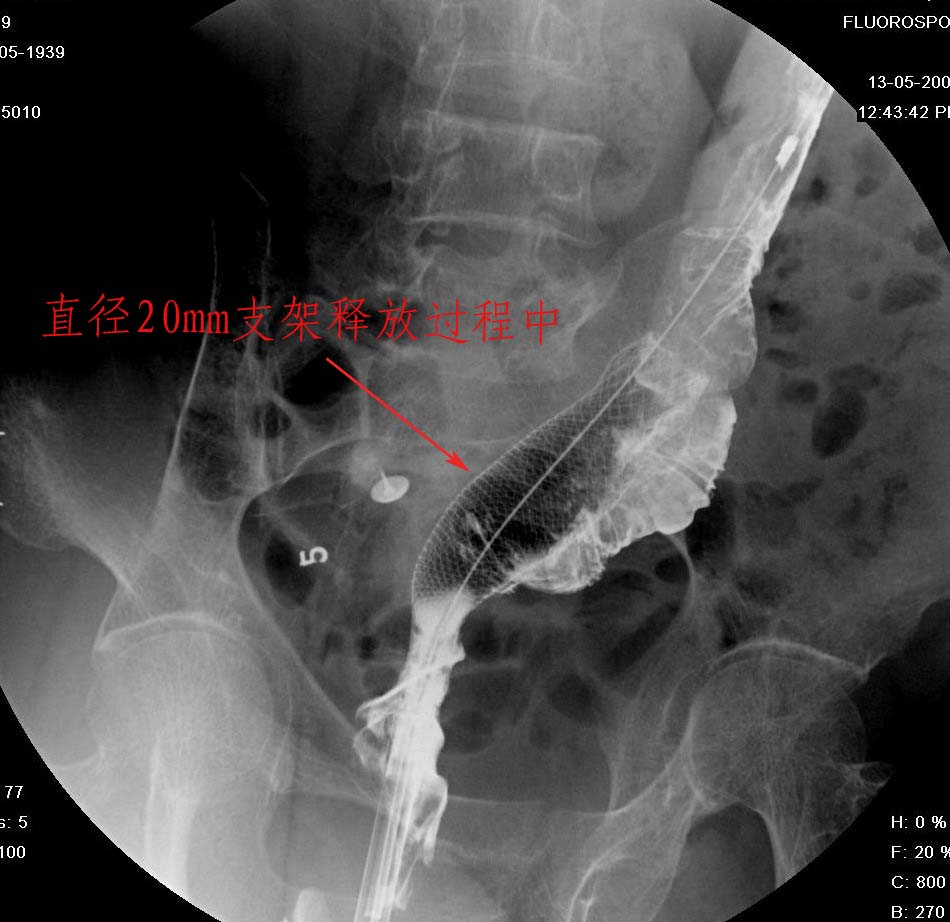

直肠癌术后两年.经过检查发现肝和腹膜后均出现转移情况,申请介入治疗.介入治疗情形见下图:

该病人用的应该是柔顺性更好的网状支架,不知道是什么品牌的.

是镍钛合金的吗?直肠还能放支架第一次见,学习。